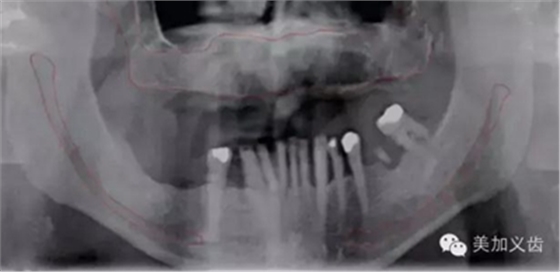

同時(shí),曲面斷層片也存在缺陷,拍攝后的影像會(huì)有放大,或者存在扭曲和變形,此時(shí)測(cè)量的數(shù)據(jù)是不可靠的。曲面斷層片在拍攝時(shí)存在結(jié)構(gòu)重疊現(xiàn)象,因此會(huì)出現(xiàn)上頜竇粘膜的假陰性和假陽(yáng)性病變,這也是其不準(zhǔn)確的地方。

如何通過(guò)曲面斷層片測(cè)量出相對(duì)準(zhǔn)確的數(shù)據(jù)?告訴大家一個(gè)很實(shí)用的方法,就是利用小剛球作為參照。

將小剛球放到口內(nèi)時(shí)拍攝曲面斷層片,拍攝后得到的結(jié)果就是這個(gè)樣子的:

因?yàn)樾偳虻闹睆绞枪潭ǖ?,通過(guò)測(cè)量片子上小剛球的直徑,就能算出曲面斷層片的放大率,然后就能算出真實(shí)的骨高度了,這是一個(gè)很不錯(cuò)的方法。